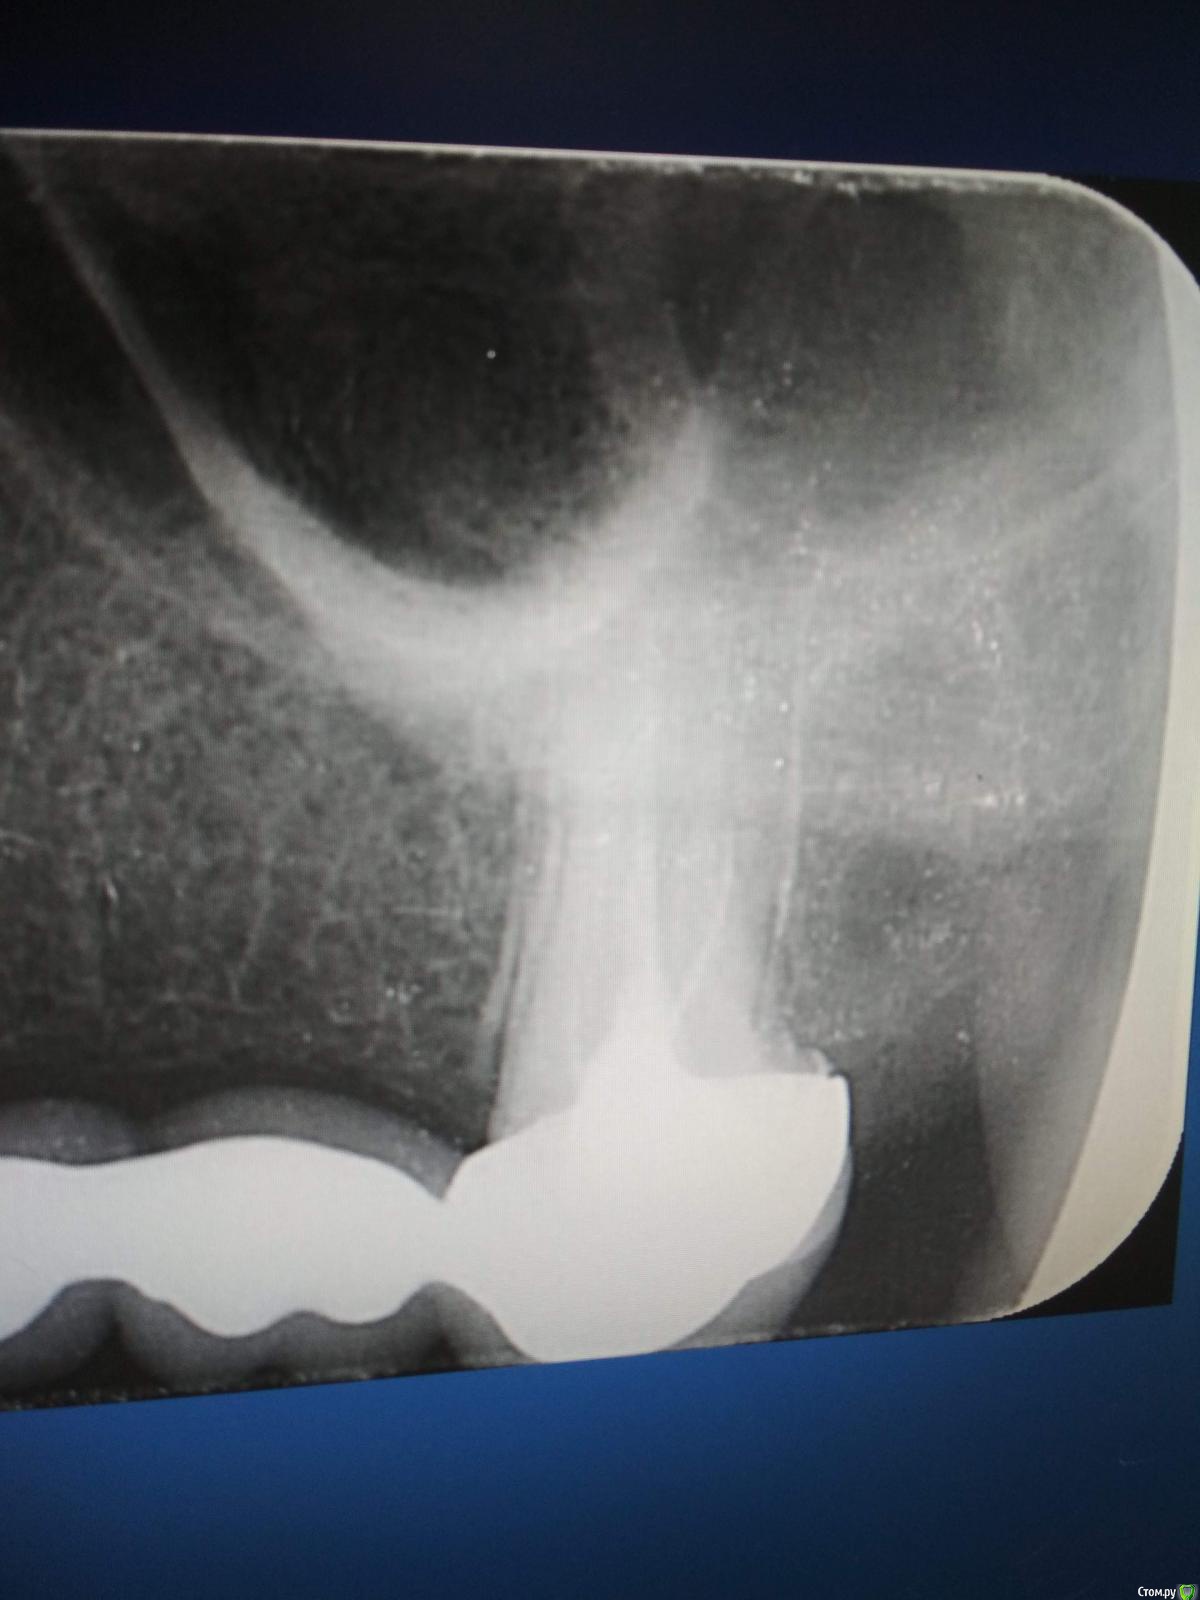

Arsinoya Опубликовано 5 октября, 2019 Автор Поделиться Опубликовано 5 октября, 2019 Прилагаю снимок Ссылка на комментарий

Arsinoya Опубликовано 5 октября, 2019 Автор Поделиться Опубликовано 5 октября, 2019 Здравствуйте, есть еще вот такой снимок, это как раз когда все боли начались, еще до перепломбировки каналов Ссылка на комментарий

Мартовский Опубликовано 7 октября, 2019 Поделиться Опубликовано 7 октября, 2019 Шестых зубов у вас нет, ни с лева ни с права, ни с верху ни с низу. Перфорация есть в левой четверке. Что делать, вам уже сказали: обратиться к другому врачу, по интернету такое не вылечить. Ссылка на комментарий